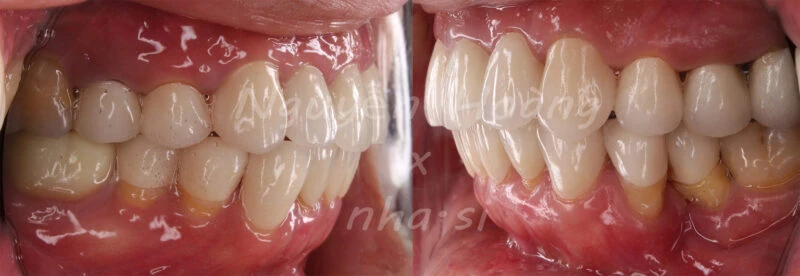

Hình 5: Sau gắn. Khách hàng hài lòng với bộ răng sứ thẩm mỹ.Nhìn từ phía ngoài, vị trí răng 5 được chụp sứ “làm đầy” hơn so với vị trí răng cũ.